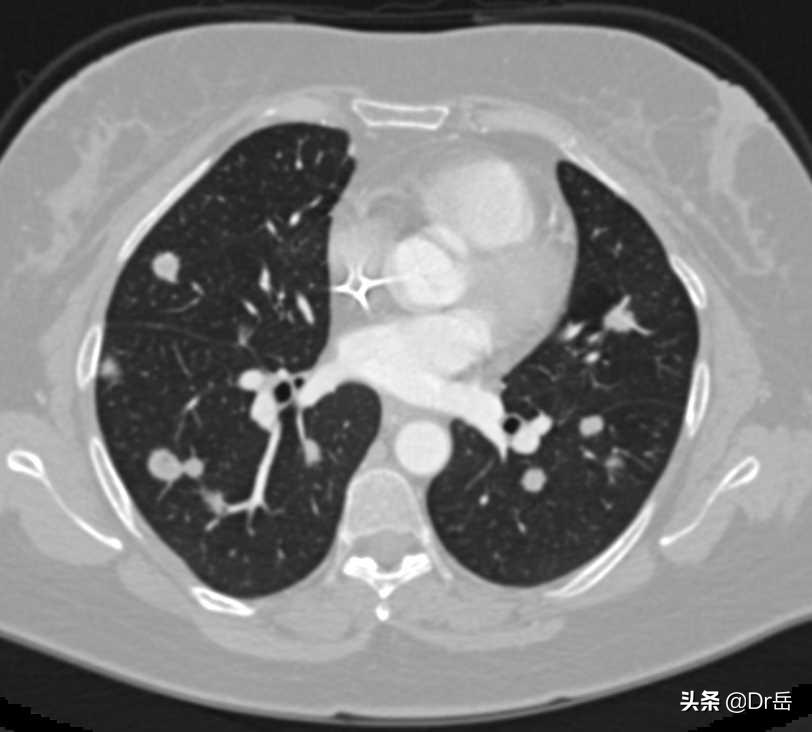

CT:肾癌肺转移灶

CT:肾癌肺转移